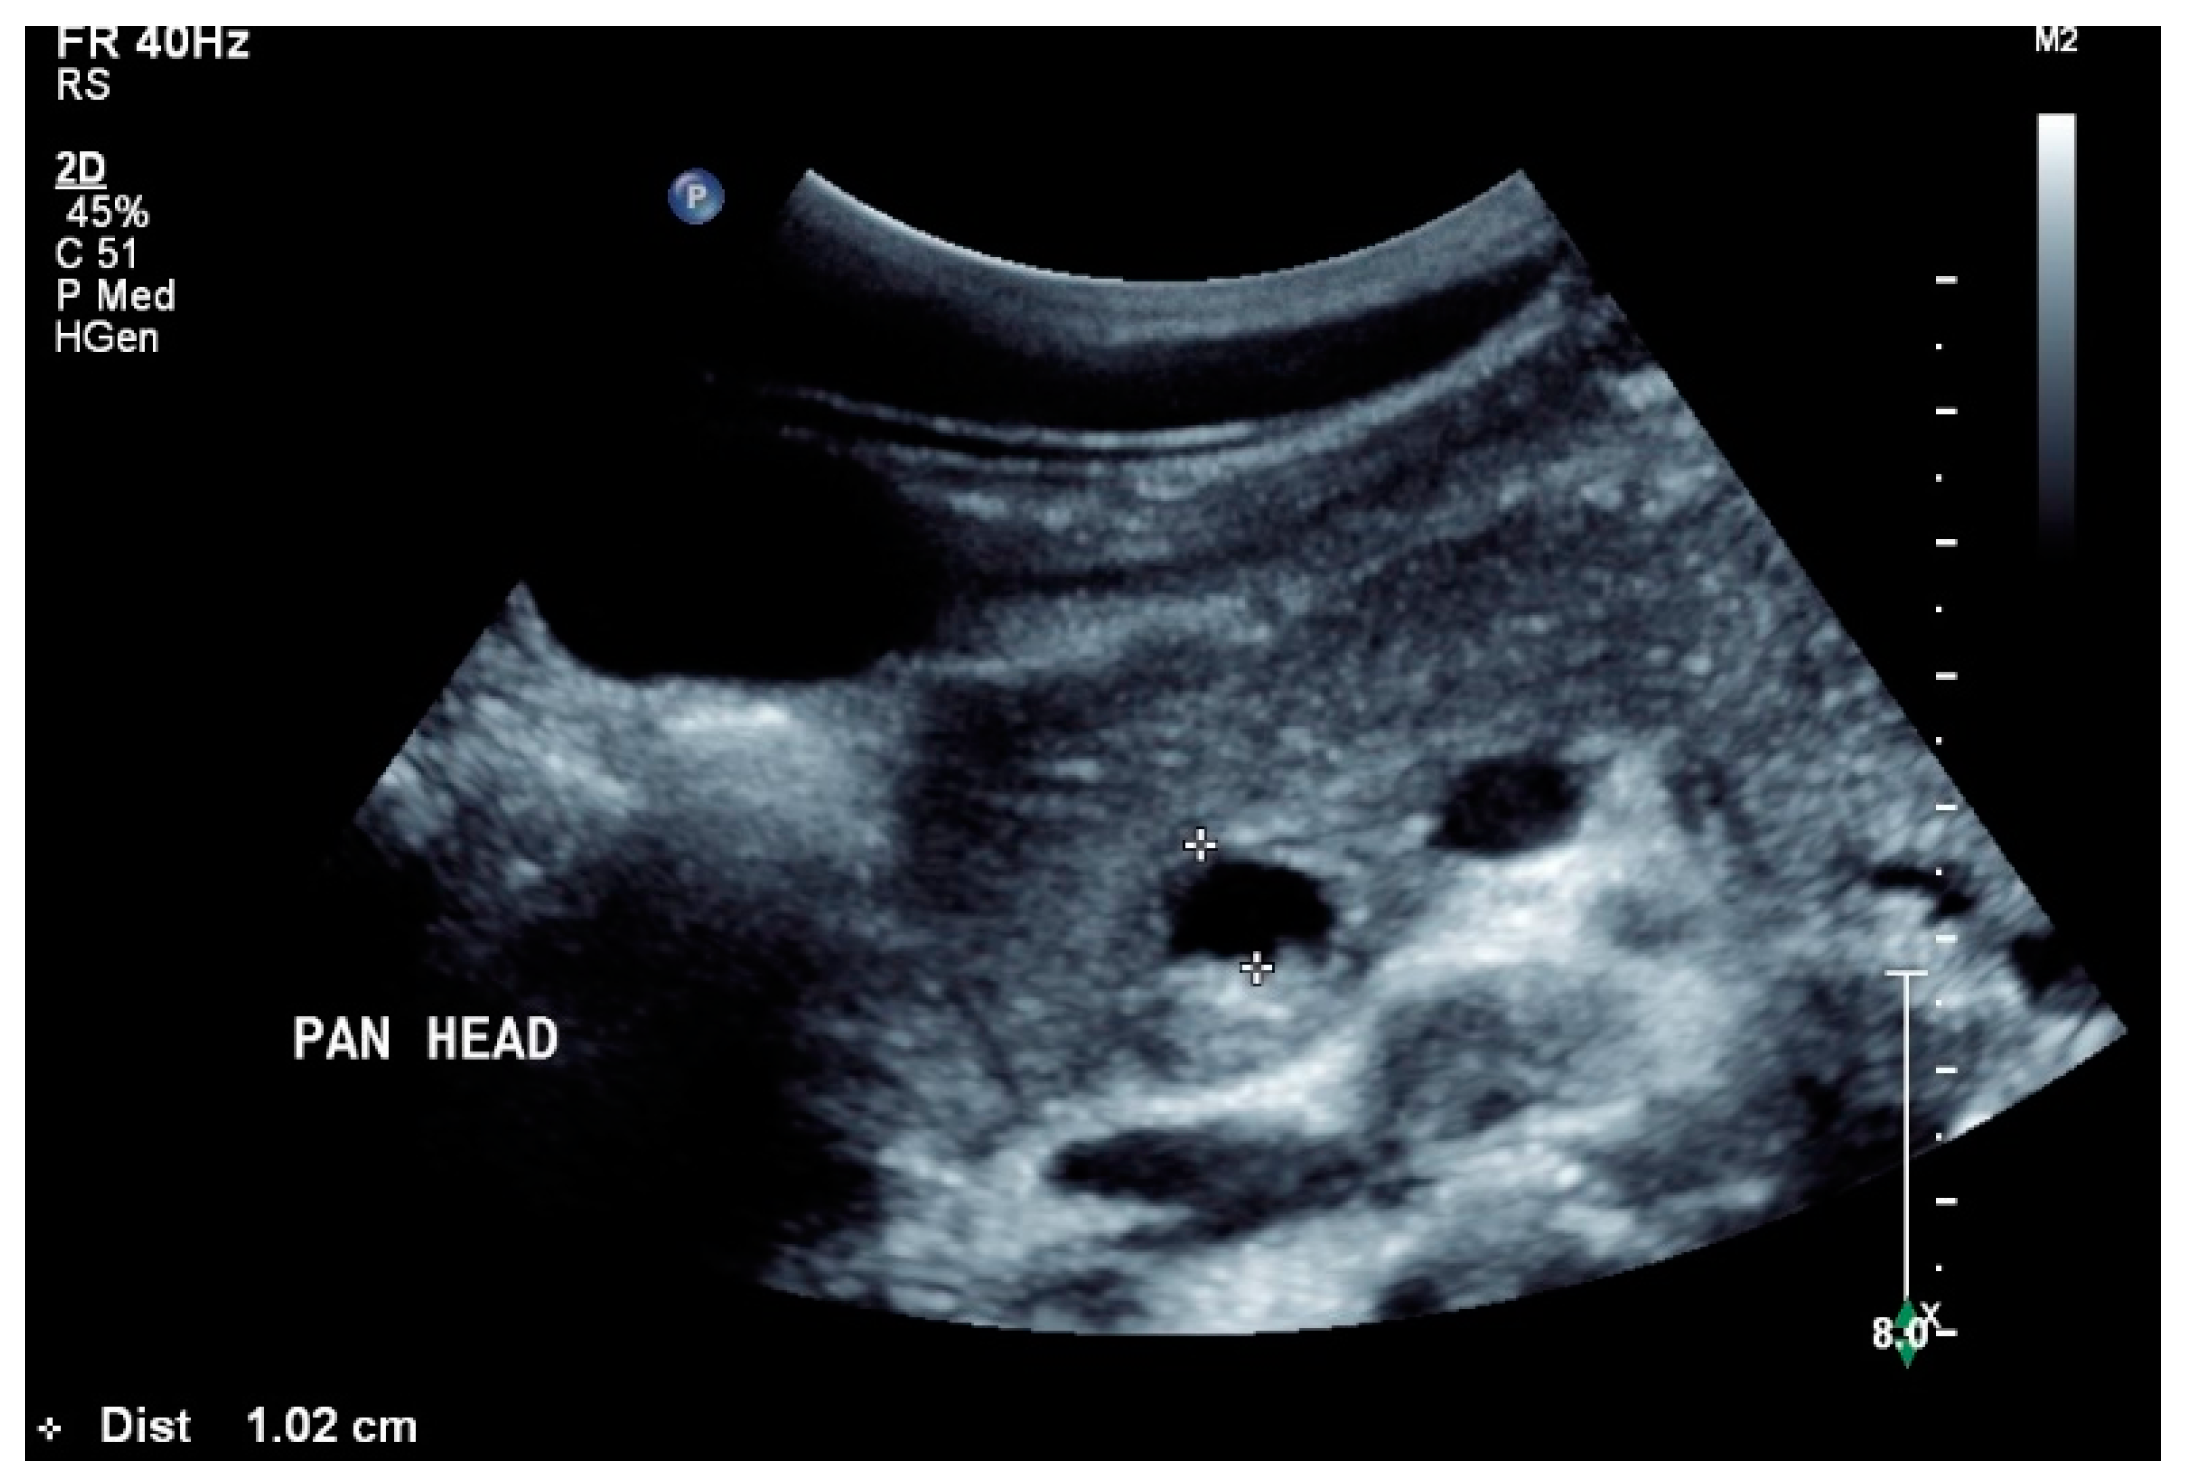

In a retrospective analysis of 384 patients with abdominal tuberculosis, 8.3% had pancreatic manifestations. In more than 50% (18/32), the pancreas with peripancreatic involvement was the primary manifestation of tuberculosis. Furthermore, 53% were HIV-positive, but only 15% presented amylase or lipase elevation [79]. Ultrasound showed a diffusely heterogeneous pancreas in 15%, as well as solitary or multiple pancreatic lesions in all patients [Figure 5]. Most lesions were hypoechoic (90.6%), and few were isoechoic (9.4%). Multiple lesions were detected in 37.5%, and solitary lesions in 63.5%, respectively. The pancreatic duct was not generally dilated [79]. Additionally, 75% of patients had concomitant peripancreatic lymphadenopathy. A characteristic feature of these lymph nodes were the hypoechoic central parts [79]. EUS showed hypoechoic or mixed cystic solid lesions, as well as often showing calcifications. Using EUS, peripancreatic lymph nodes as well as mediastinal lymph node enlargements were detected simultaneously [80,81,82,83,84]. Both the pancreatic lesions and the peripancreatic and mediastinal lymph nodes can be subjected to EUS-guided biopsy [46,83,85]. In a study of 12 patients with solitary pancreatic tuberculosis manifestations, typical imaging findings when using CEUS were hyper- or isoenhancement in the arterial phase, and hypoenhancement in the late phase [83]. Using CH-EUS, the examined lesions showed hyperenhancement. In ultrasound elastography and EUS elastography, the tuberculosis lesions were stiffer than the surrounding area. EUS elastography showed that the stiffness was dependent on the stage of the disease [83]. The common bile duct was not dilated [83]. Using EUS-FNA, pancreatic/peripancreatic tuberculosis was correctly diagnosed in 76.2% of cases [86]. Diagnostically significant in the EUS-FNP are granulomatous inflammation, a positive tuberculosis polymerase chain reaction test, Ziehl–Neelsen staining, and positive cultures of Mycobacterium tuberculosis [86]. A calcified lesion with a cheesy core observed during macroscopic on-site evaluation should be examined for tuberculosis [46]. The most important differential diagnoses are pancreatic ductal adenocarcinoma, pancreatic neuroendocrine neoplasia (PanNEN), metastases, autoimmune pancreatitis and lymphoma manifestations [83,85,87], or cystic neoplasms [88].

Figure 5.

Pancreatic tuberculosis. Plump large pancreas. There is a lesion with a thick echogenic capsule and hyperechogenic and anechoic contents (between the markers) at the head of the pancreas. This finding was evaluated as a caseous abscess in a patient with tuberculosis.